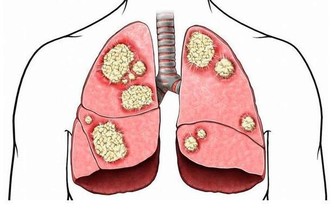

腫瘤部位不同,症狀也不同

同是大腸癌病友,但每個人的情況也會不一樣。

這是因為,長在不同部位的腫瘤,表現出來的症狀不一樣。

降結腸、乙狀結腸、直腸的癌症:腸道狹窄,再加上腸道蠕動活躍,就會出現便秘與腹瀉交替出現的情況。

還有,糞便通過時,會擦到腫瘤表面,引起出血。

癌症導致的出血若長期持續,就會出現貧血。

升結腸、橫結腸的癌症:症狀更難察覺。這些部位與小腸相連,小腸運來的糞便還處於液態,

即使此處有癌腫出血,出血量也不會太多,肉眼很難觀察到。

但如果出血時間長,會出現貧血,很多人都是出現貧血才發現大腸癌的。

所以,貧血是大腸癌的共同症狀。

另外,盲腸、升結腸、橫結腸中的癌腫變大後,撫摸肚子會感覺有小疙瘩或硬塊,

而在降結腸、乙狀結腸、直腸的位置,即使癌症處於進展期,也難以觸摸到疙瘩狀的腫塊。

小貼士:大腸癌的症狀、便秘、腹瀉反復發生;

有血便和便血;糞便細;腹部有腫塊;

總感覺排便沒有排完全;腹痛;有貧血症狀。